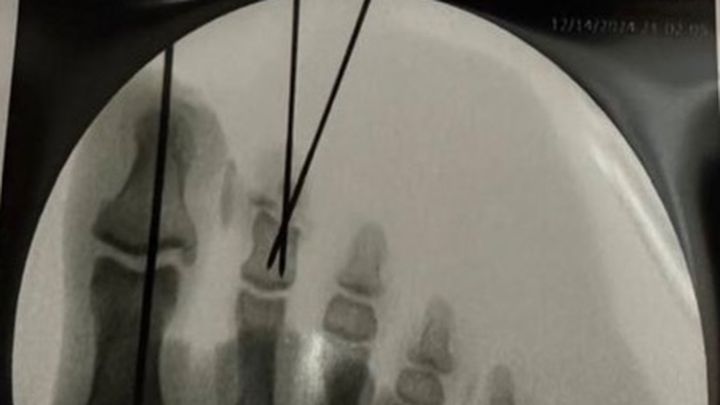

Currently I’m in the hospital recovering from the surgery and I will have metal pins sticking out of my toes to keep them together for the next month, while I’m on crutches.

Yesterday I had an accident while trimming some trees with a chainsaw and severely damaged my big toe and 2nd toe. Having gone through emergency surgery, it still remains to be seen if the 2nd toe will need to be partially amputated if there isn’t enough circulation.

UPDATE: I am now home, changing bandages around the pins in the big toe and the 2nd toe… on Wednesday we find out for certain if the 2nd toe is salvageable or will need to be partially amputated. Doctor has a positive outlook as he sees circulation at the part that was severed.

Today at a follow-up appointment the orthopedic surgeon made the decision that a joint amputation will NOT be necessary! This is a BiG WiN as that would’ve affected balance and function!